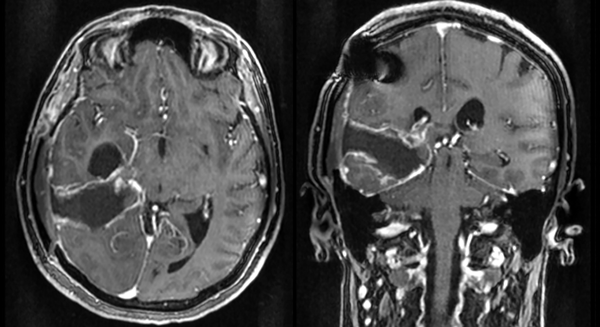

Se realizaron controles periódicos, con buena evolución de las funciones cognitivas, aunque el déficit visual persistió, presumiblemente por isquemia de un segmento del área visual primaria (dependiente de la cerebral posterior) o por daño a las radiaciones ópticas temporales. Se efectuó RM de control a los dos meses de la intervención, objetivándose una óptima resección tumoral (Figura 3).

Figura 3. RM con gadolinio en secuencia T1, corte axial a la izquierda, coronal a la derecha. Se observa una buena resección, con un posible remanente tumoral residual hacia la porción más medial.